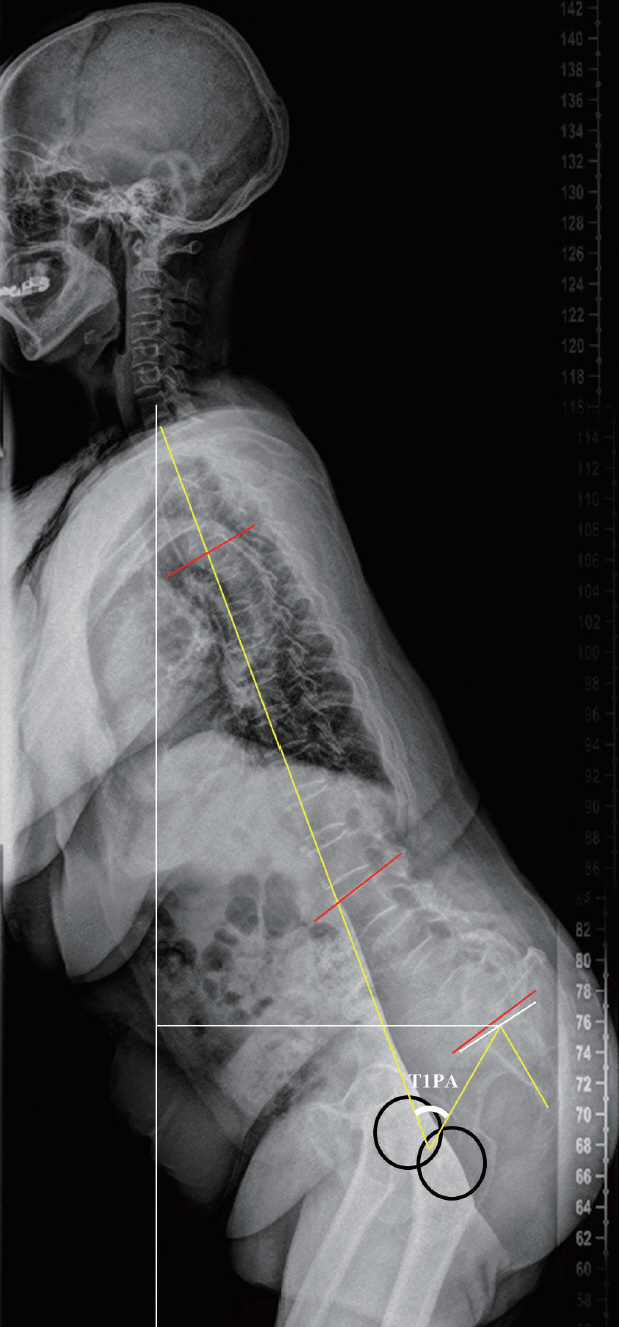

: A total of 46 participants were farmers, and the others were housewives, sellers, and office workers. The farmer group had more SVA (141 vs. 99 mm, p=0.001) and pelvic tilt (31° vs. 24°, p=0.004) and lesser lumbar lordosis (20° vs. 30°, p=0.009) and thoracic kyphosis (24° vs. 33°, p=0.03) than non-farmer group. A significantly positive correlation was noted between the working hour and SVA in the farmer group (p=0.014). The visual analogue scale score for back pain (8.26 vs. 6.96, p=0.008) and Oswestry Disability Index (23.5 vs. 19.1, p=0.003) in the farmer group were higher than that in the non-farmer group, but the Short Form-36 score was not significantly different between the two groups. The Mini-Mental State Exam score was significantly lower in the farmer group than in the non-farmer group (24.85 vs. 26.98, p=0.002).

Article19. Protopsaltis T, Schwab F, Bronsard N, Smith JS, Klineberg E, Mundis G, et al. TheT1 pelvic angle, a novel radiographic measure of global sagittal deformity, accounts for both spinal inclination and pelvic tilt and correlates with health-related quality of life. J Bone Joint Surg Am. 96:1631–1640. 2014.